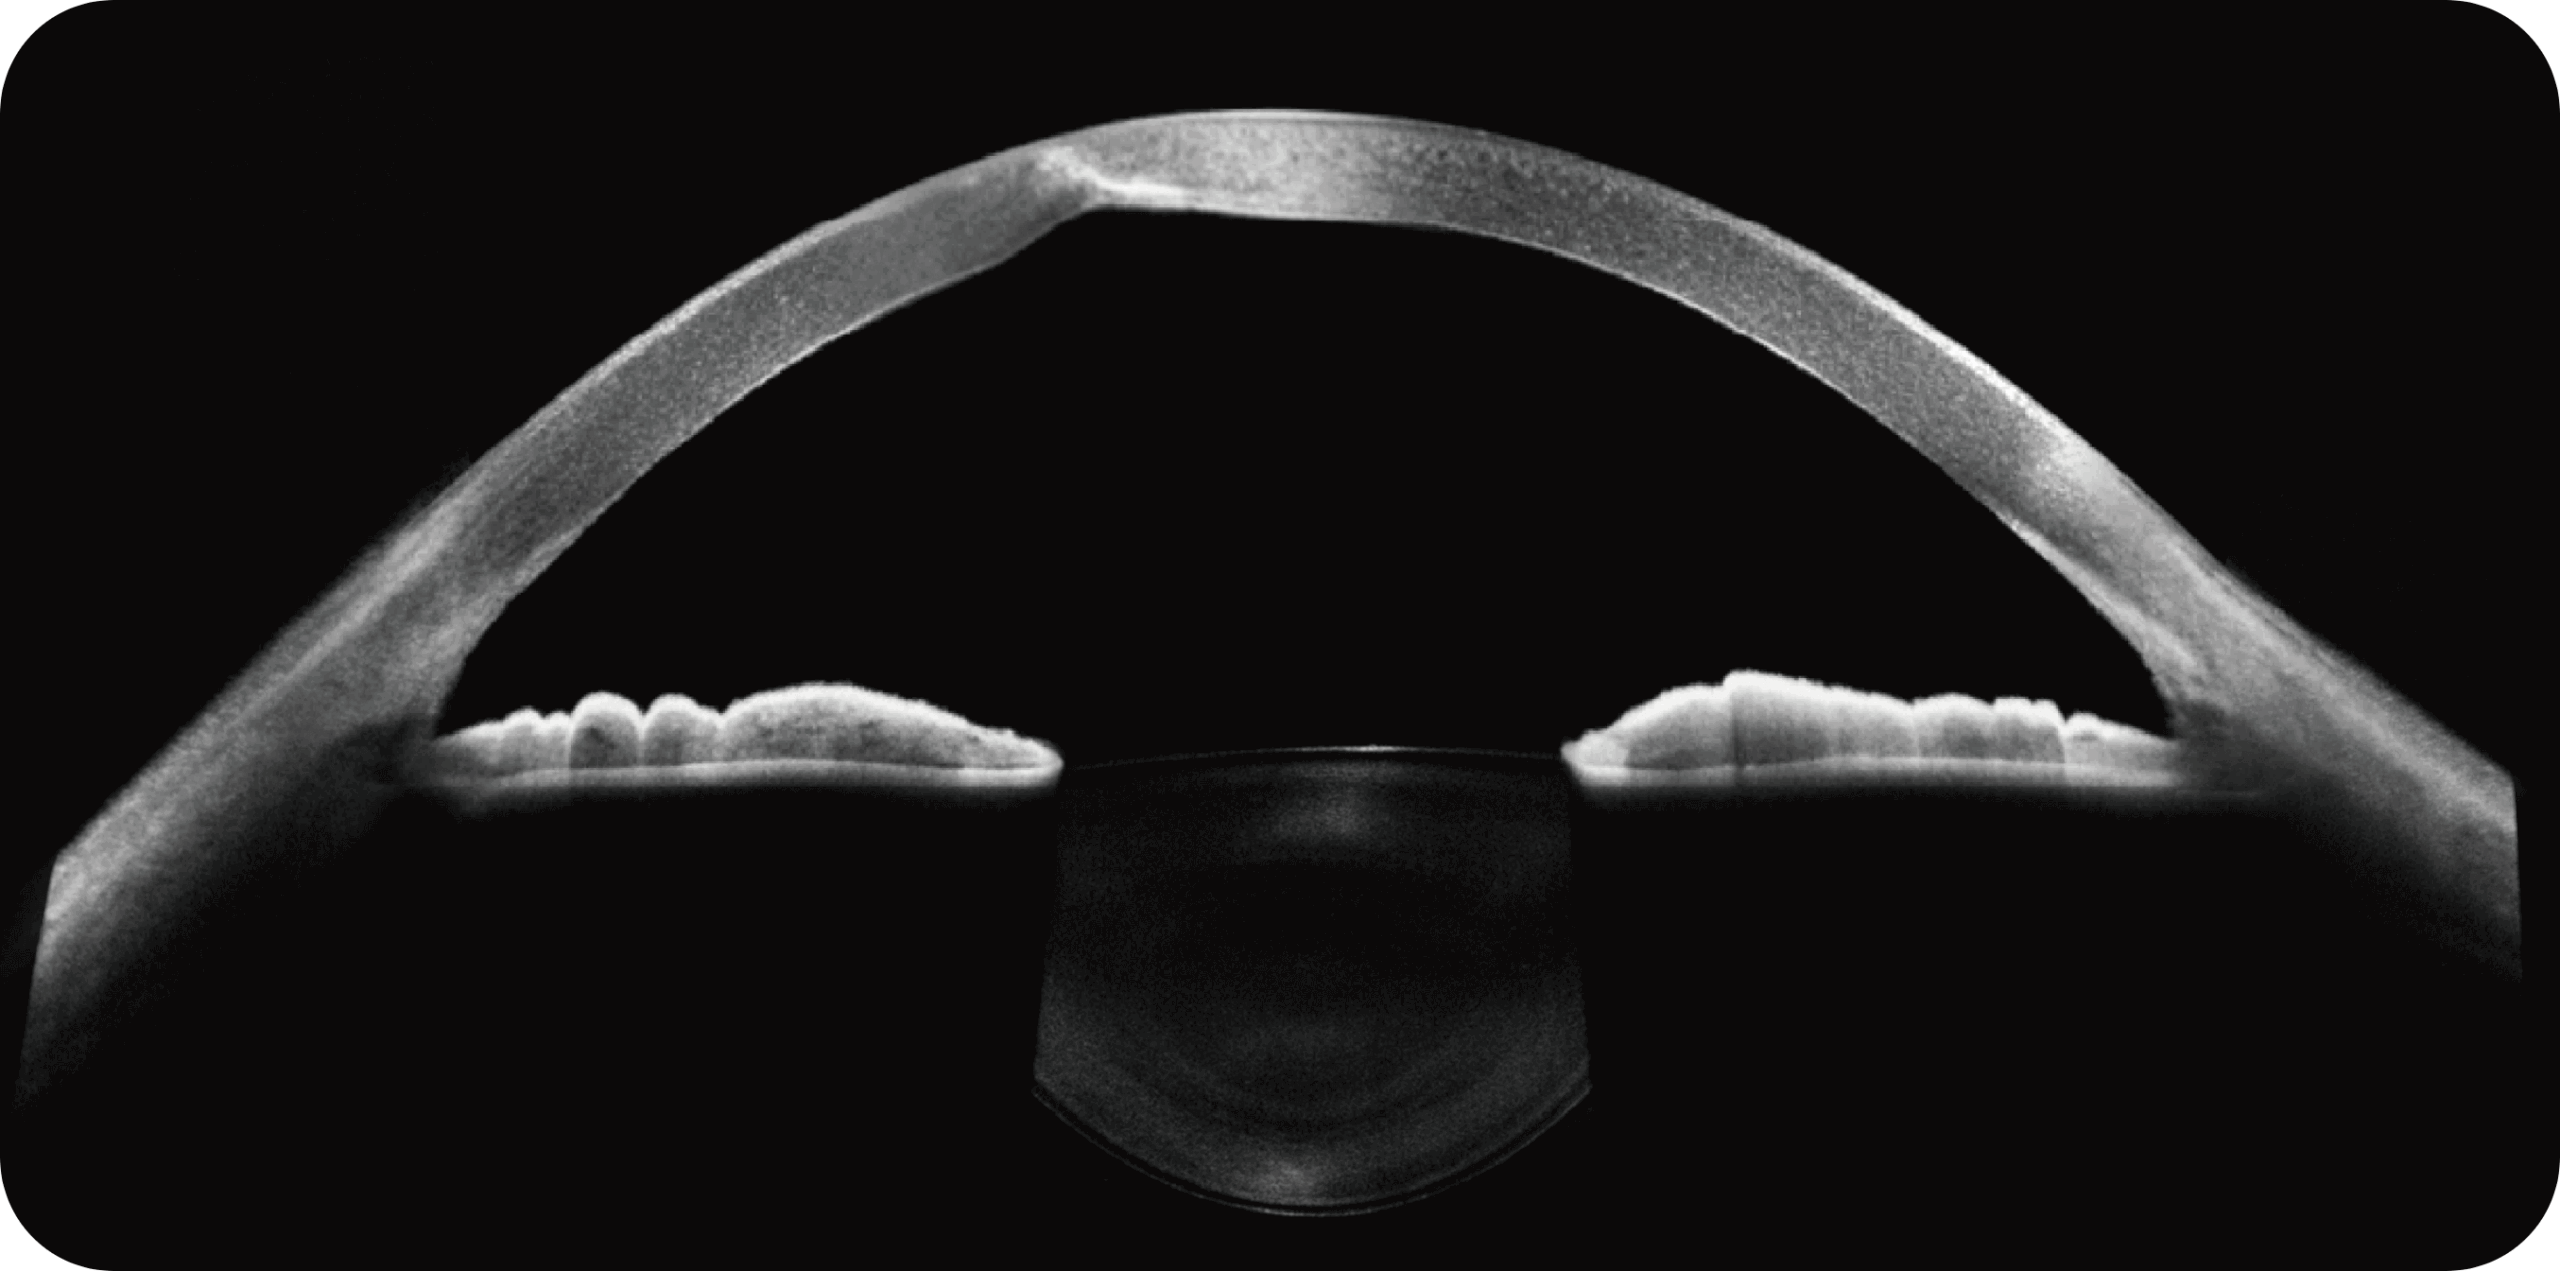

Altamente integrado com tecnologias como SLO confocal e SS-OCT, ele combina imagens coloridas SLO de campo ultralargo, angiografia confocal a laser, autofluorescência e imagens tomográficas de segmento anterior e posterior ultraamplas e profundas em um único sistema.

Exames de segmento anterior com OCT de 28mm.